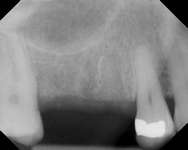

Figure 1A through Figure 1C Buccal and radiographic views of posterior edentulism with significant sinus pneumatization in the molar region.

Figure 1D Lateral wall osteotomy.

Figure 1E The osteotomy was grafted with particulate bone. Figure 1F The surgical site was covered with a resorbable barrier.

Figure 1G Radiographic confirmation of bone regeneration 8 months after surgery. Figure 1H Radiographic confirmation of implant osteointegration into the new bone 14 months after the initial surgery. Figure 1I. Final implant-supported restoration.